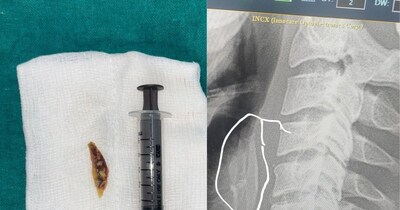

- •पन्ना में सेवानिवृत्त सीएमएचओ और वरिष्ठ सर्जन डॉ. एच.एम. शर्मा ने 500 ग्राम की पथरी सफलतापूर्वक निकाली.

- •इस जटिल ऑपरेशन से इटवा गांव के युवक बुद्ध सिंह को 18 साल के मूत्राशय की पथरी के दर्द से राहत मिली.

- •जांच में असामान्य रूप से बड़ी पथरी का पता चला, जिससे सर्जरी ही एकमात्र विकल्प बचा था.

- •कई घंटों तक चला यह ऑपरेशन डॉ. शर्मा के करियर का सबसे चुनौतीपूर्ण मामला था, क्योंकि पथरी का आकार और जोखिम बहुत अधिक था.